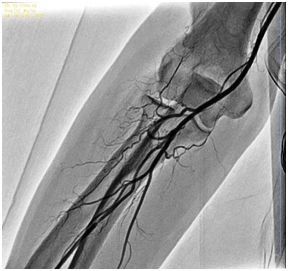

RAA are relatively common in general population, although there are limited data concerning this issue worldwide [4]. Their incidence may vary according to the available literature, starting from 8,8% [7,6], 13,8% [2], up to 22,8% according to Valsecchi et al. [3]. They can be reason for procedural failure in 1-5% of the patients even in experienced operators` hands [4,9]. RAA include high bifurcating origin of the radial artery (high take-off radial artery) (Figure 1), radial artery loop (Figure 2 & 3), tortuosity (Figure 1), hypoplasia and stenosis. In most cases, these anomalies can be overcome by using hydrophilic guiding wire and diagnostic 5F Judkins right catheter (JR 4) or even 4F Judkins right catheter, sometimes 0,014” hydrophilic coronary wire [1] and in rare cases by using so-called BAT technique (“balloon-assisted tracking”), a technique proposed by Dr. Tejas Patel et al. [9]. Operators should be experienced in TRA and by using some simple maneuvers like push-and-pull technique and catheter rotation usually achieve a successful negotiation with the radial artery (Figure 4).

Figure 3: Radial artery loop with remnant artery.